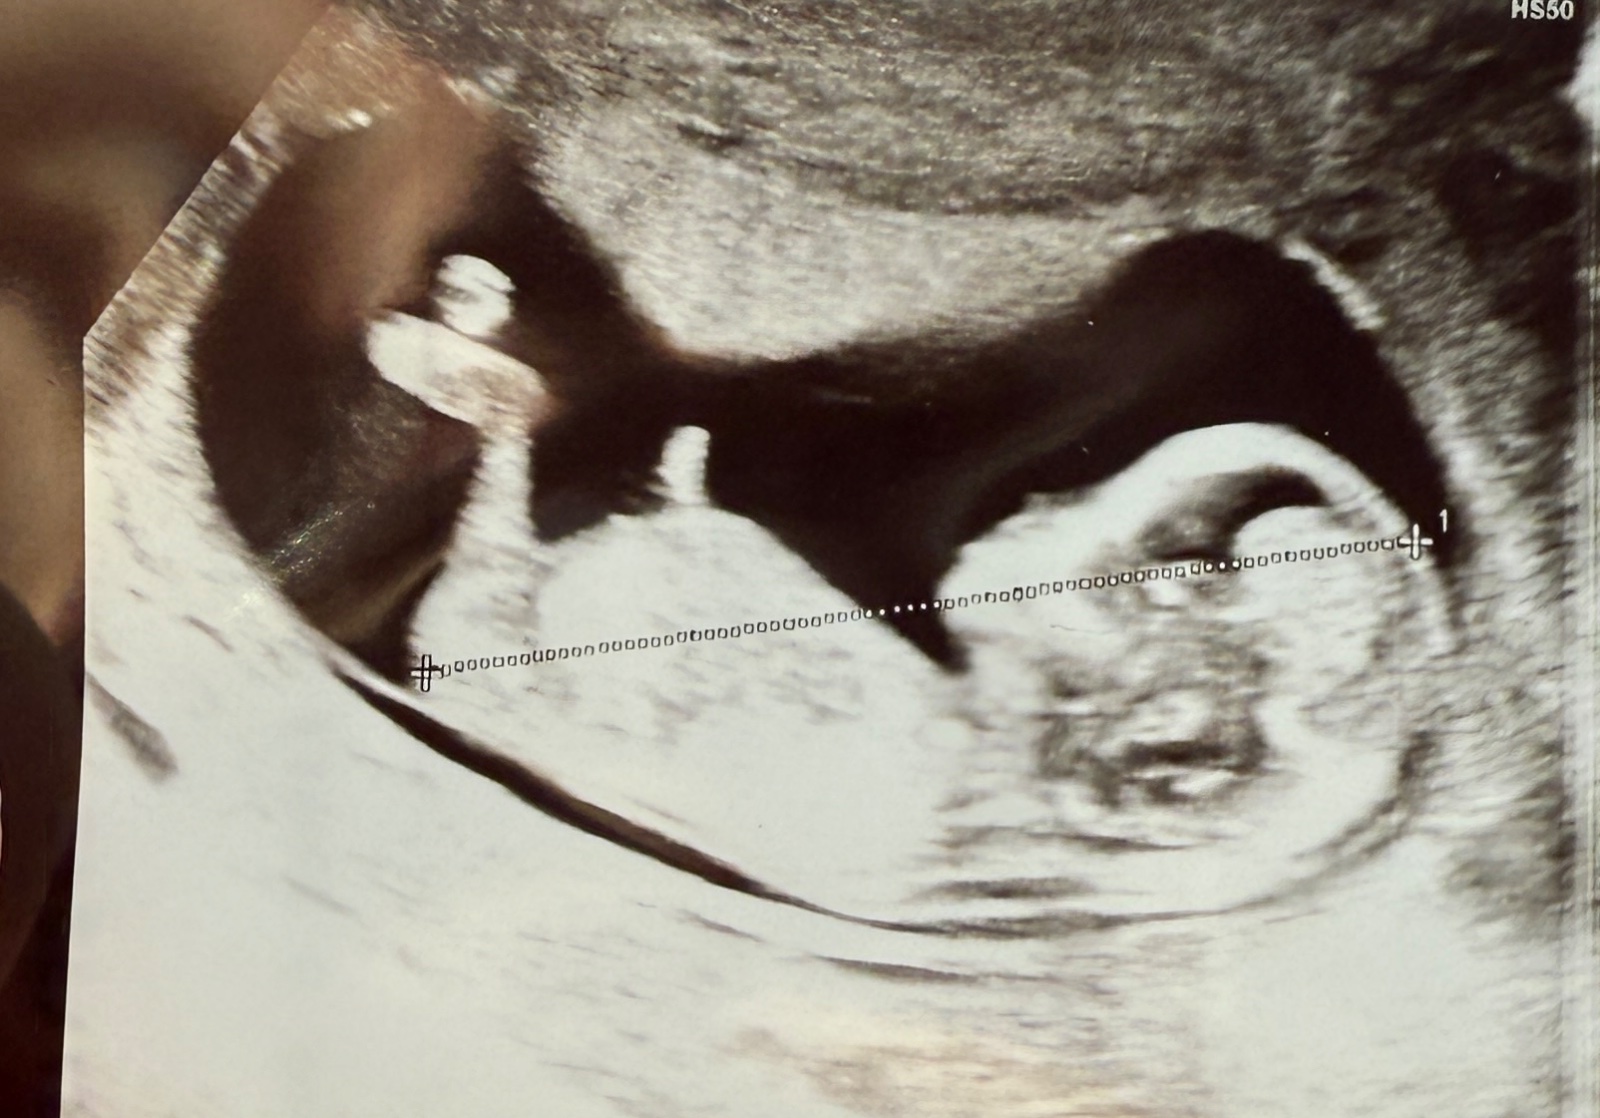

hodila som to do chatgpt:

ak je fotka zhruba medzi 11. a 14. týždňom tehotenstva (čo podľa veľkosti bábätka na obrázku aj sedí), tak sa dá teoreticky skúsiť odhad cez "nub theory". Tá hovorí:

Ak výčnelok (nub) smeruje rovno (0–30°) od chrbtice, ide pravdepodobne o dievčatko.

Ak je pod uhlom viac ako 30° nahor, môže to byť chlapček.

Na tejto konkrétnej fotke to ale vyzerá, že nub (ak ho teda správne identifikujeme – je to ten svetlý výbežok medzi nôžkami) je relatívne rovnobežný s chrbticou, možno mierne nahor, ale určite nie pod veľkým uhlom. Takže podľa tejto teórie by to skôr vyzeralo na dievčatko. 💗

Samozrejme – je to len teória, nie zaručená metóda. Lekár určuje pohlavie spoľahlivejšie až okolo 16. – 20. týždňa.